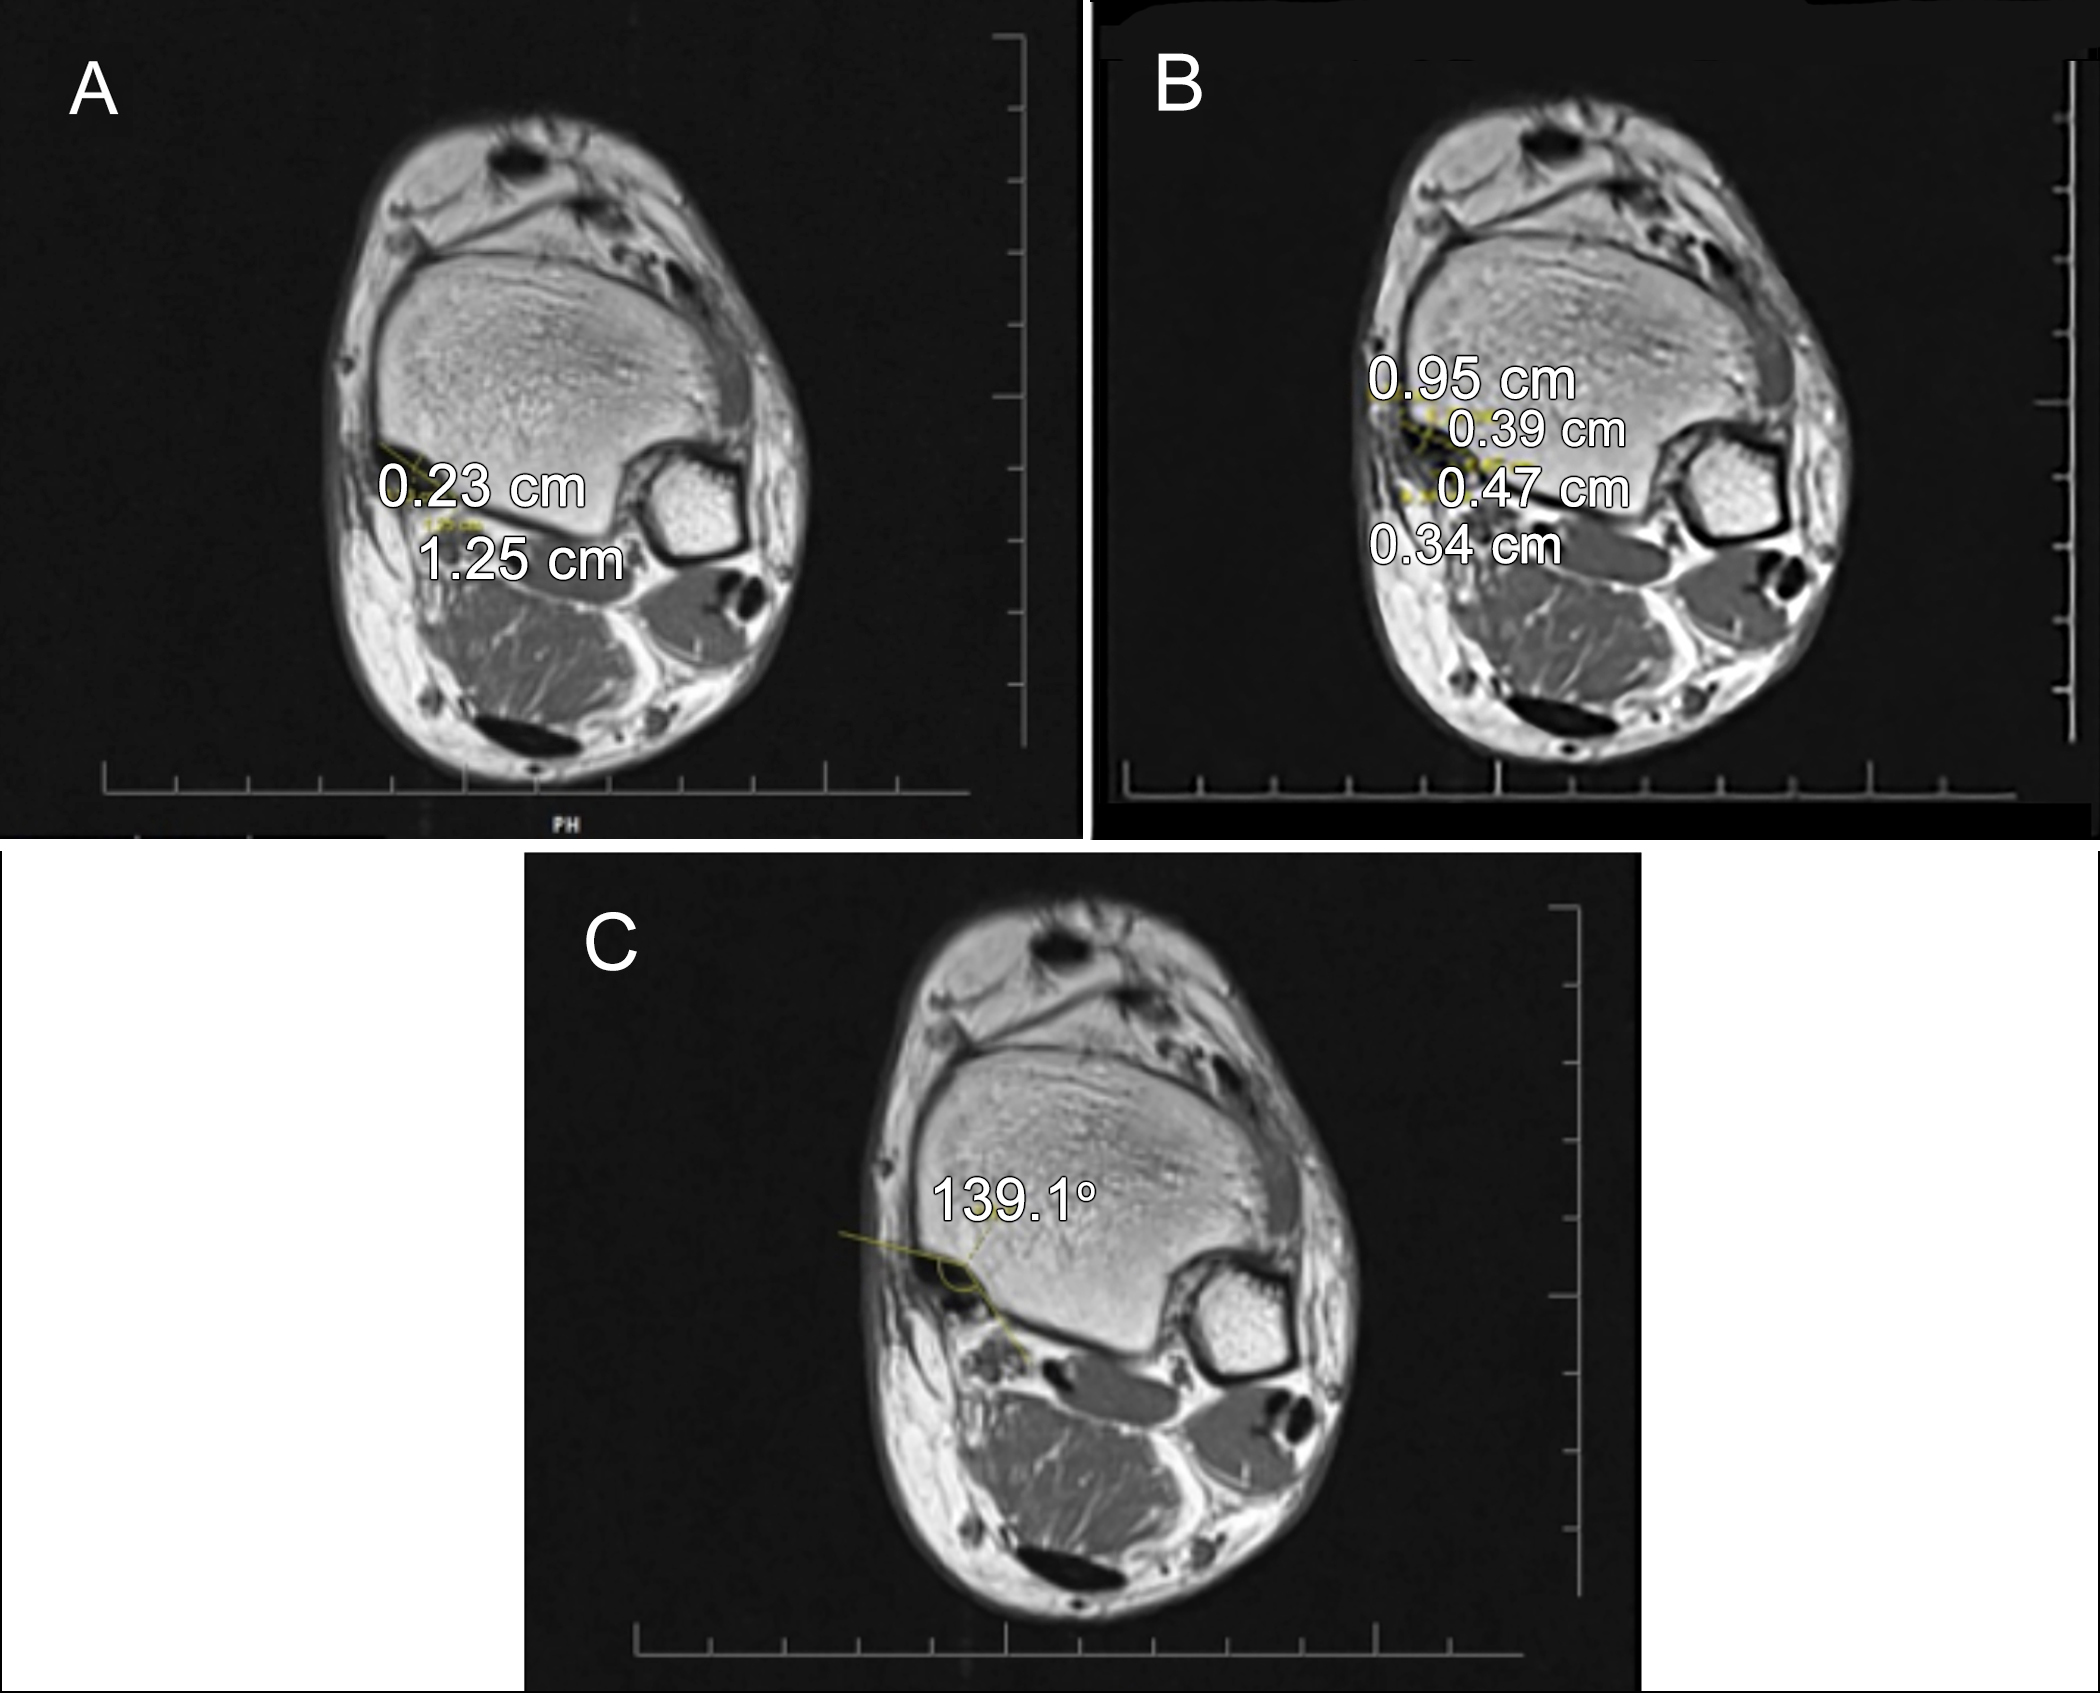

Figure 1: Medial malleolar, posterior tibial tendon (PTT), and flexor digitorum longus tendon (FDLT) measurements from the level where the groove is most prominent. (A) groove depth and width measurement. (B) PTT and FDLT width and depth measurement. (C) groove opening angle measurement.

The measurements were performed by the experienced radiologist in musculoskeletal radiology. All the measurements were taken twice and averaged. In ten patients, the measurements were repeated at one-week intervals to investigate intra-observer agreement. In addition, the measurements of 30 patients were also made by a second observer to investigate inter-observer agreement. The MMG depth and width measurements were performed in the axial plane at the level where the groove was the most prominent. The farthest distance between the both edges of the groove was defined as the width, and the vertical distance drawn from this line to the deepest part of MMG was recorded as the depth (Figure 1A). The PTT and FDLT width (transverse measurement) and thickness (anteroposterior length) measurements were undertaken in the same plane (Figure 1B). The groove length was determined on the axial plane images by first determining the MMG start and end levels, and then measuring the distance between the two levels on the sagittal images. The groove opening angle (GOA) was measured as the angle between the two ends of the groove width and its deepest part in the axial plane (Figure 1C). The shortest distance from the posterior border of MMG to the level of syndesmosis articulation in the lateral was recorded as the posterior PM (PPM) length. The total PM (TPM) length was measured from the anterior border of MMG as the shortest distance from the lateral syndesmosis articulation. The measurement performed from the middle part of the tibia, where it was the thickest, was noted as the anterior PM (APM) length. All the three measurements are shown in Figure 2.